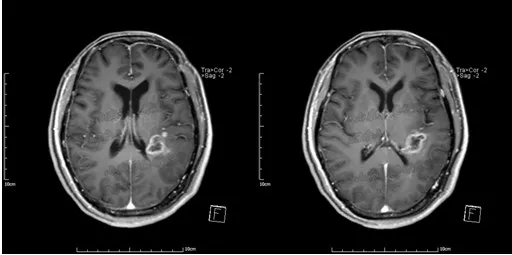

磁共振图清晰显示了满女士手术后复发病变情况

医生说,该病变在脑内位置较深,与周围组织关系复杂,手术完全切除难度较大。